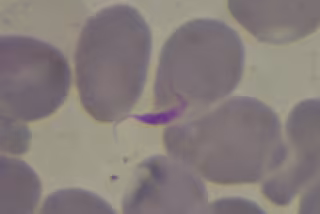

Parásito del Chagas

Un nuevo estudio revela que las enfermedades transmitidas por vectores y parásitos tienen consecuencias importantes para el desarrollo económico en todo el mundo y son los principales causantes de las diferencias de ingresos entre los países tropicales y templados, según los resultados de la investigación, publicados en la revista Plos Biology'.

Aunque es común a la conclusión de que la economía impulsa el patrón de la enfermedad, los autores señalan que la mayoría de las enfermedades que afligen a los países pobres gastan la mayor parte de su ciclo de vida fuera del huésped humano. Muchos ni siquiera pueden sobrevivir fuera de los trópicos y su distribución está determinada en gran medida por factores ecológicos, como la temperatura, las precipitaciones y la calidad del suelo.